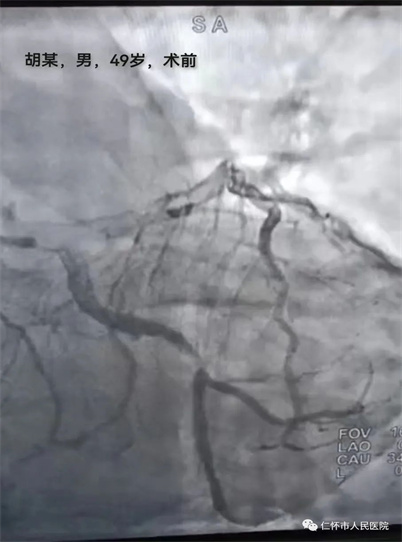

5月27日上午,急诊科接诊了一名58岁胡姓胸痛高危患者,当班医生徐力主治医师接诊后详询病史,患者自述突发胸痛、胸闷,逐转至抢救室,给予心电监护、吸氧,建立静脉通路,床旁查体,急查心电图及心梗三项检查,心电图结果提示急性下壁心肌梗塞,立即抢救,急请心血管内科医师会诊,当班医生一边说一边展开抢救。在予扩管、抗凝、抗血小板等药物治疗后,患者胸痛症状稍有缓解。经心血管内科医师苏如袖会诊后建议立即行急诊介入手术。就在这万分紧急时又再次接诊一位49岁胡姓胸痛患者,急诊科医师徐力立即上报余兴素总住院医师参与抢救,经询问病史、查体及相关辅查后患者同样诊断为急性下壁心肌梗死,但目前只有一个空台可以手术,这似乎多了那么一丝微妙在其中,为了两名患者得到有效的快速救治,我院急诊科副主任医师罗杨松及苏如袖医师当机立断,根据两名患者心电图情况一名患者立即行经皮冠状动脉介入治疗(PCI),另一名患者急诊溶栓后再行介入。